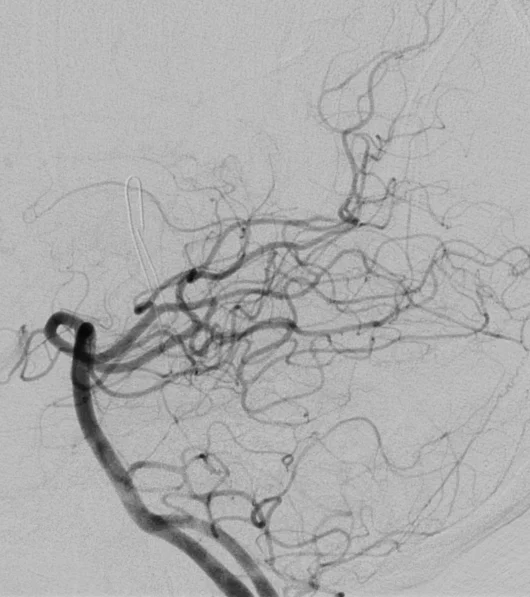

Cet examen invasif, réalisé sous anesthésie locale, permet d’obtenir une analyse morphologique et dynamique très précise des artères et des veines du cerveau ou de la moelle épinière en rendant les vaisseaux sanguins visibles aux rayons X en y injectant un produit de contraste à l’aide d’un tuyau (cathéter) que l’on navigue sous contrôle radiologique depuis le poignet ou le pli inguinal.

L’angiographie cérébrale est un examen diagnostic qui permet de visualiser les vaisseaux qui amènent le sang au cerveau (artères) et ceux qui le ramènent vers le coeur (veines). Les termes artériographie et phlébographie désignent respectivement l’étude spécifique des artères et des veines. Lorsque l’on s’intéresse aux vaisseaux de la moëlle épinière, on parle d’angiographie médullaire.

L’objectif est de rechercher une anomalie des vaisseaux pouvant expliquer vos symptômes. comme une malformation des vaisseaux (anévrysme, malformation artério-veineuse, fistule…), un rétrécissement ou l’occlusion totale d’une artère.

Afin d’éviter les infections, le médecin qui pratique l’examen porte une tenue “stérile”. L’équipe paramédicale désinfecte la peau à hauteur du pli de l’aine et/ou du poignet (le plus souvent à droite). On vous recouvre ensuite d’un champ stérile avec un ou des orifices permettant de travailler. Une anesthésie locale est pratiquée en regard de l’artère fémorale ou radiale et un petit tuyau (introducteur) y est placé. Cet accès permet ensuite de coulisser un second tuyau (cathéter) qui sera guidé par le médecin sous contrôle radiologique jusqu’aux artères que l’on souhaite étudier. Plusieurs séries d’images sont alors réalisées en injectant du produit de contraste iodé dans le flux sanguin à l’aide du cathéter et en faisant des radiographies dynamiques de de ce “moulage” des vaisseaux. A chaque injection, vous pouvez ressentir une sensation de chaleur dans la tête, une sensation de vertige, un goût métallique, des scintillements visuels. Ces symptômes durent quelques secondes et disparaissent ensuite complètement.